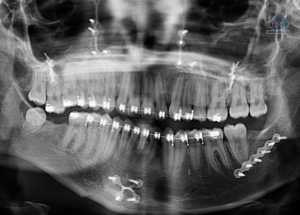

Caso 300 – IDM – HIPERPLASIA DE APÓFISIS CORONOIDES DE LADO DERECHO – IDM

Paciente femenino de 16 años acude al Instituto de Diagnóstico Maxilofacial (sede Miraflores) para evaluación quirúrgica. Radiografia Panorámica A la evaluación de la radiografía panorámica